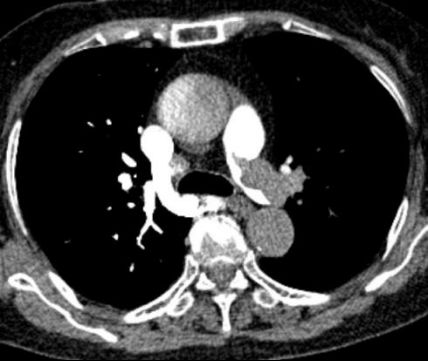

急诊医生快速研判,高度怀疑为急性肺栓塞。肺动脉CTA检查结果证实了判断:双侧肺动脉主干及分支存在多处血栓栓塞,右心室明显扩大——这是急性肺栓塞的典型征象,说明肺动脉堵塞已导致右心室负荷急剧增加,心脏功能受损。

图:胸部增强CT(CTPA)示右肺动脉主干及分支内可见多发充盈缺损提示肺动脉栓塞